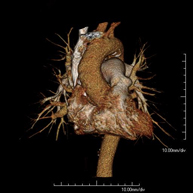

- Coronary CT angiography or Coronary CT

The Coronary CT angiography or non-invasive Coronarography is a diagnostic test to examine arteries of the heart, or coronary arteries, using state-of-the-art MDCT equipment and an iodinated contrast agent to obtain two- and three-dimensional images. Multidetector computed tomography (MDCT) entails high-speed imaging that is beneficial in assessing coronary arteries with high anatomical precision, particularly in evaluating narrowing or stenosis, calcifications, anatomical variants, etc., as its speed prevents the artefact caused by the constant movement of the heart (1,000 images can be obtained in less than 10 seconds). The information obtained requires processing at workstations equipped with specialised software capable of reconstructing the coronary arteries, thereby enabling an assessment to be made of the number, location and characteristics of the lesions. All this information is obtained non-invasively, involving a simple puncture of a peripheral vein (in the arm). To ensure the heart rate stays below 75 bpm, some patients will need preliminary treatment with beta blockers.